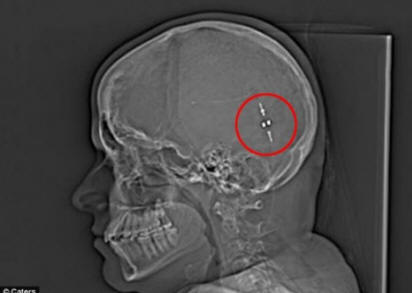

Ale poté, co našli způsob, jak odstranit přebytečnou tekutinu její mozek do břicha, její život se změnil. Drain, také známý jako gastroperitoneální zkrat, propojující mozek a žaludek, což mu umožňuje tráví mozkovou tekutinu a snižuje tlak na mozek.

Lidský mozek je obklopen tekutinou, která ho chrání od nárazu na lebku, ale Samovo tělo se ukázalo být vytváří tuto tekutinu třikrát více, než je norma. I poté diagnostikovat a brát 17 různých drog denně, Sam i nadále trpěl strašnými bolestmi hlavy.

A teprve v květnu loňského roku dostala dívka zkratku vypouštění přebytečné tekutiny. Sam doufal v okamžitou úlevu, ale trvalo jí mozek, než si zvykla na cizí tělo. Po nějaké době se Samův mozek od té doby přizpůsobil změnám pak znovu žije normálním životem. Životní čas